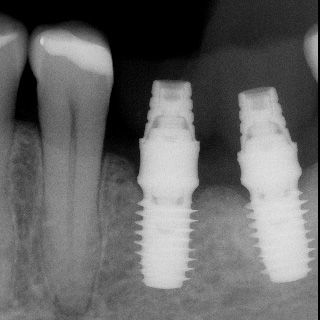

NeoArch

El Sistema de Implantes NeoArch® de Neodent® ofrece una solución optimizada para protocolos de tratamiento de arco fijo inmediato para pacientes edéntulos, incluso en casos con maxilares severamente atróficos.

NeoArch® está diseñado para aumentar la satisfacción del paciente y la calidad de vida al restaurar inmediatamente la función y la estética.

Solución para arcada completa

Tecnología del Sistema Grand Morse®

Concepto de Cuerpo Helix®

Muñón Cónico Mini